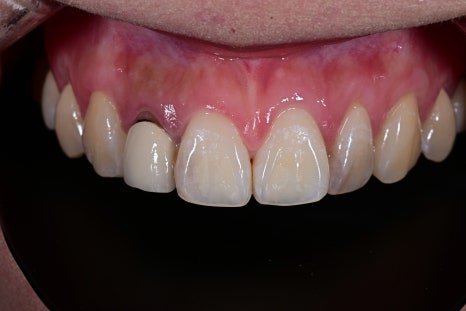

<BEFORE>

Natural appearance of the gum line restored

A color harmony with the surrounding teeth

Improvement of the sense of incongruity in the front teeth

The response that it “looks like a natural tooth”

was especially impressive.